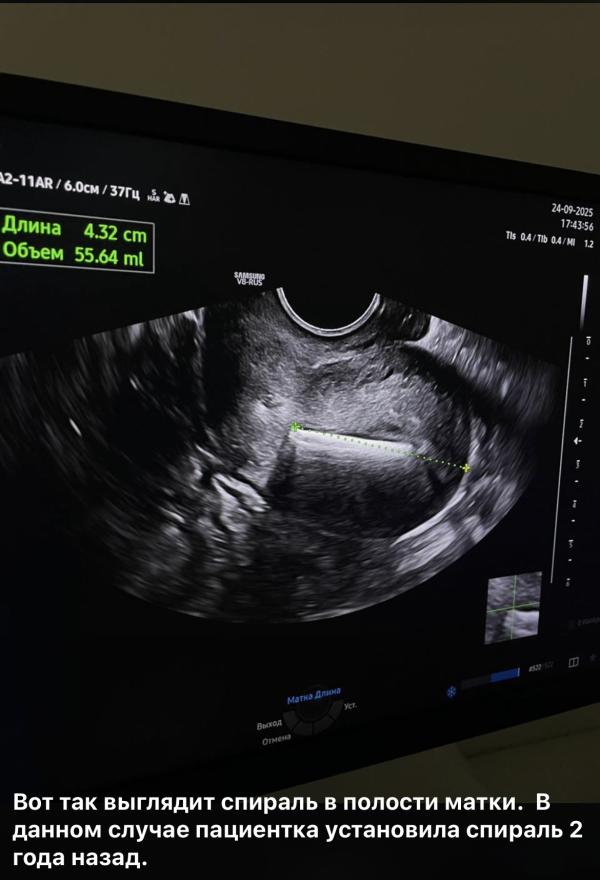

Какие анализы нужны перед установкой спирали ВМС

Базовые обязательные исследования перед установкой внутриматочной спирали:

1. УЗИ органов малого таза